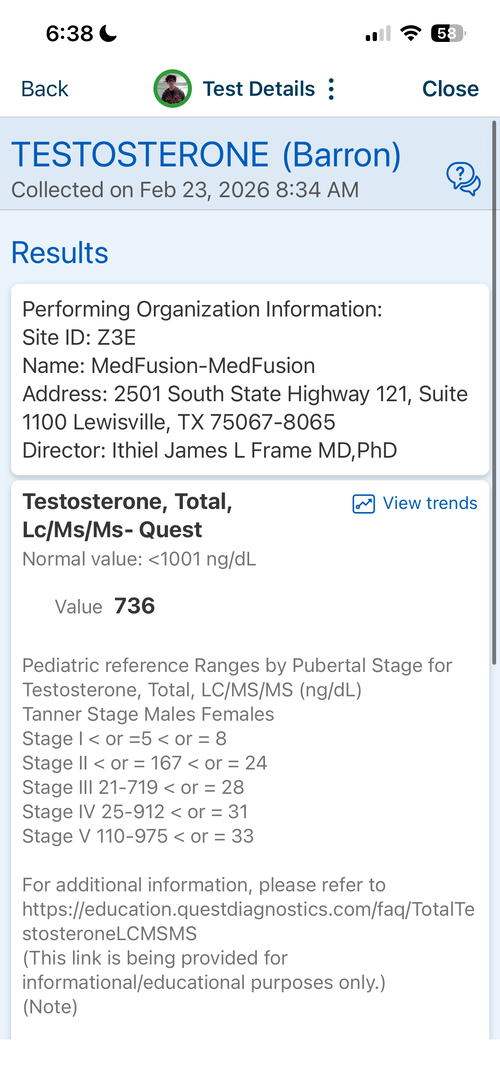

16.6 yr old male at 5'11.1" in height currently. Father is 6'1.5" and Mother is 5'8". I have images of my growth chart along with an X-Ray of my wrist attached. I also attached recent bloodwork tests of TESTOSTERONE, IGF-1 and Cortisol.